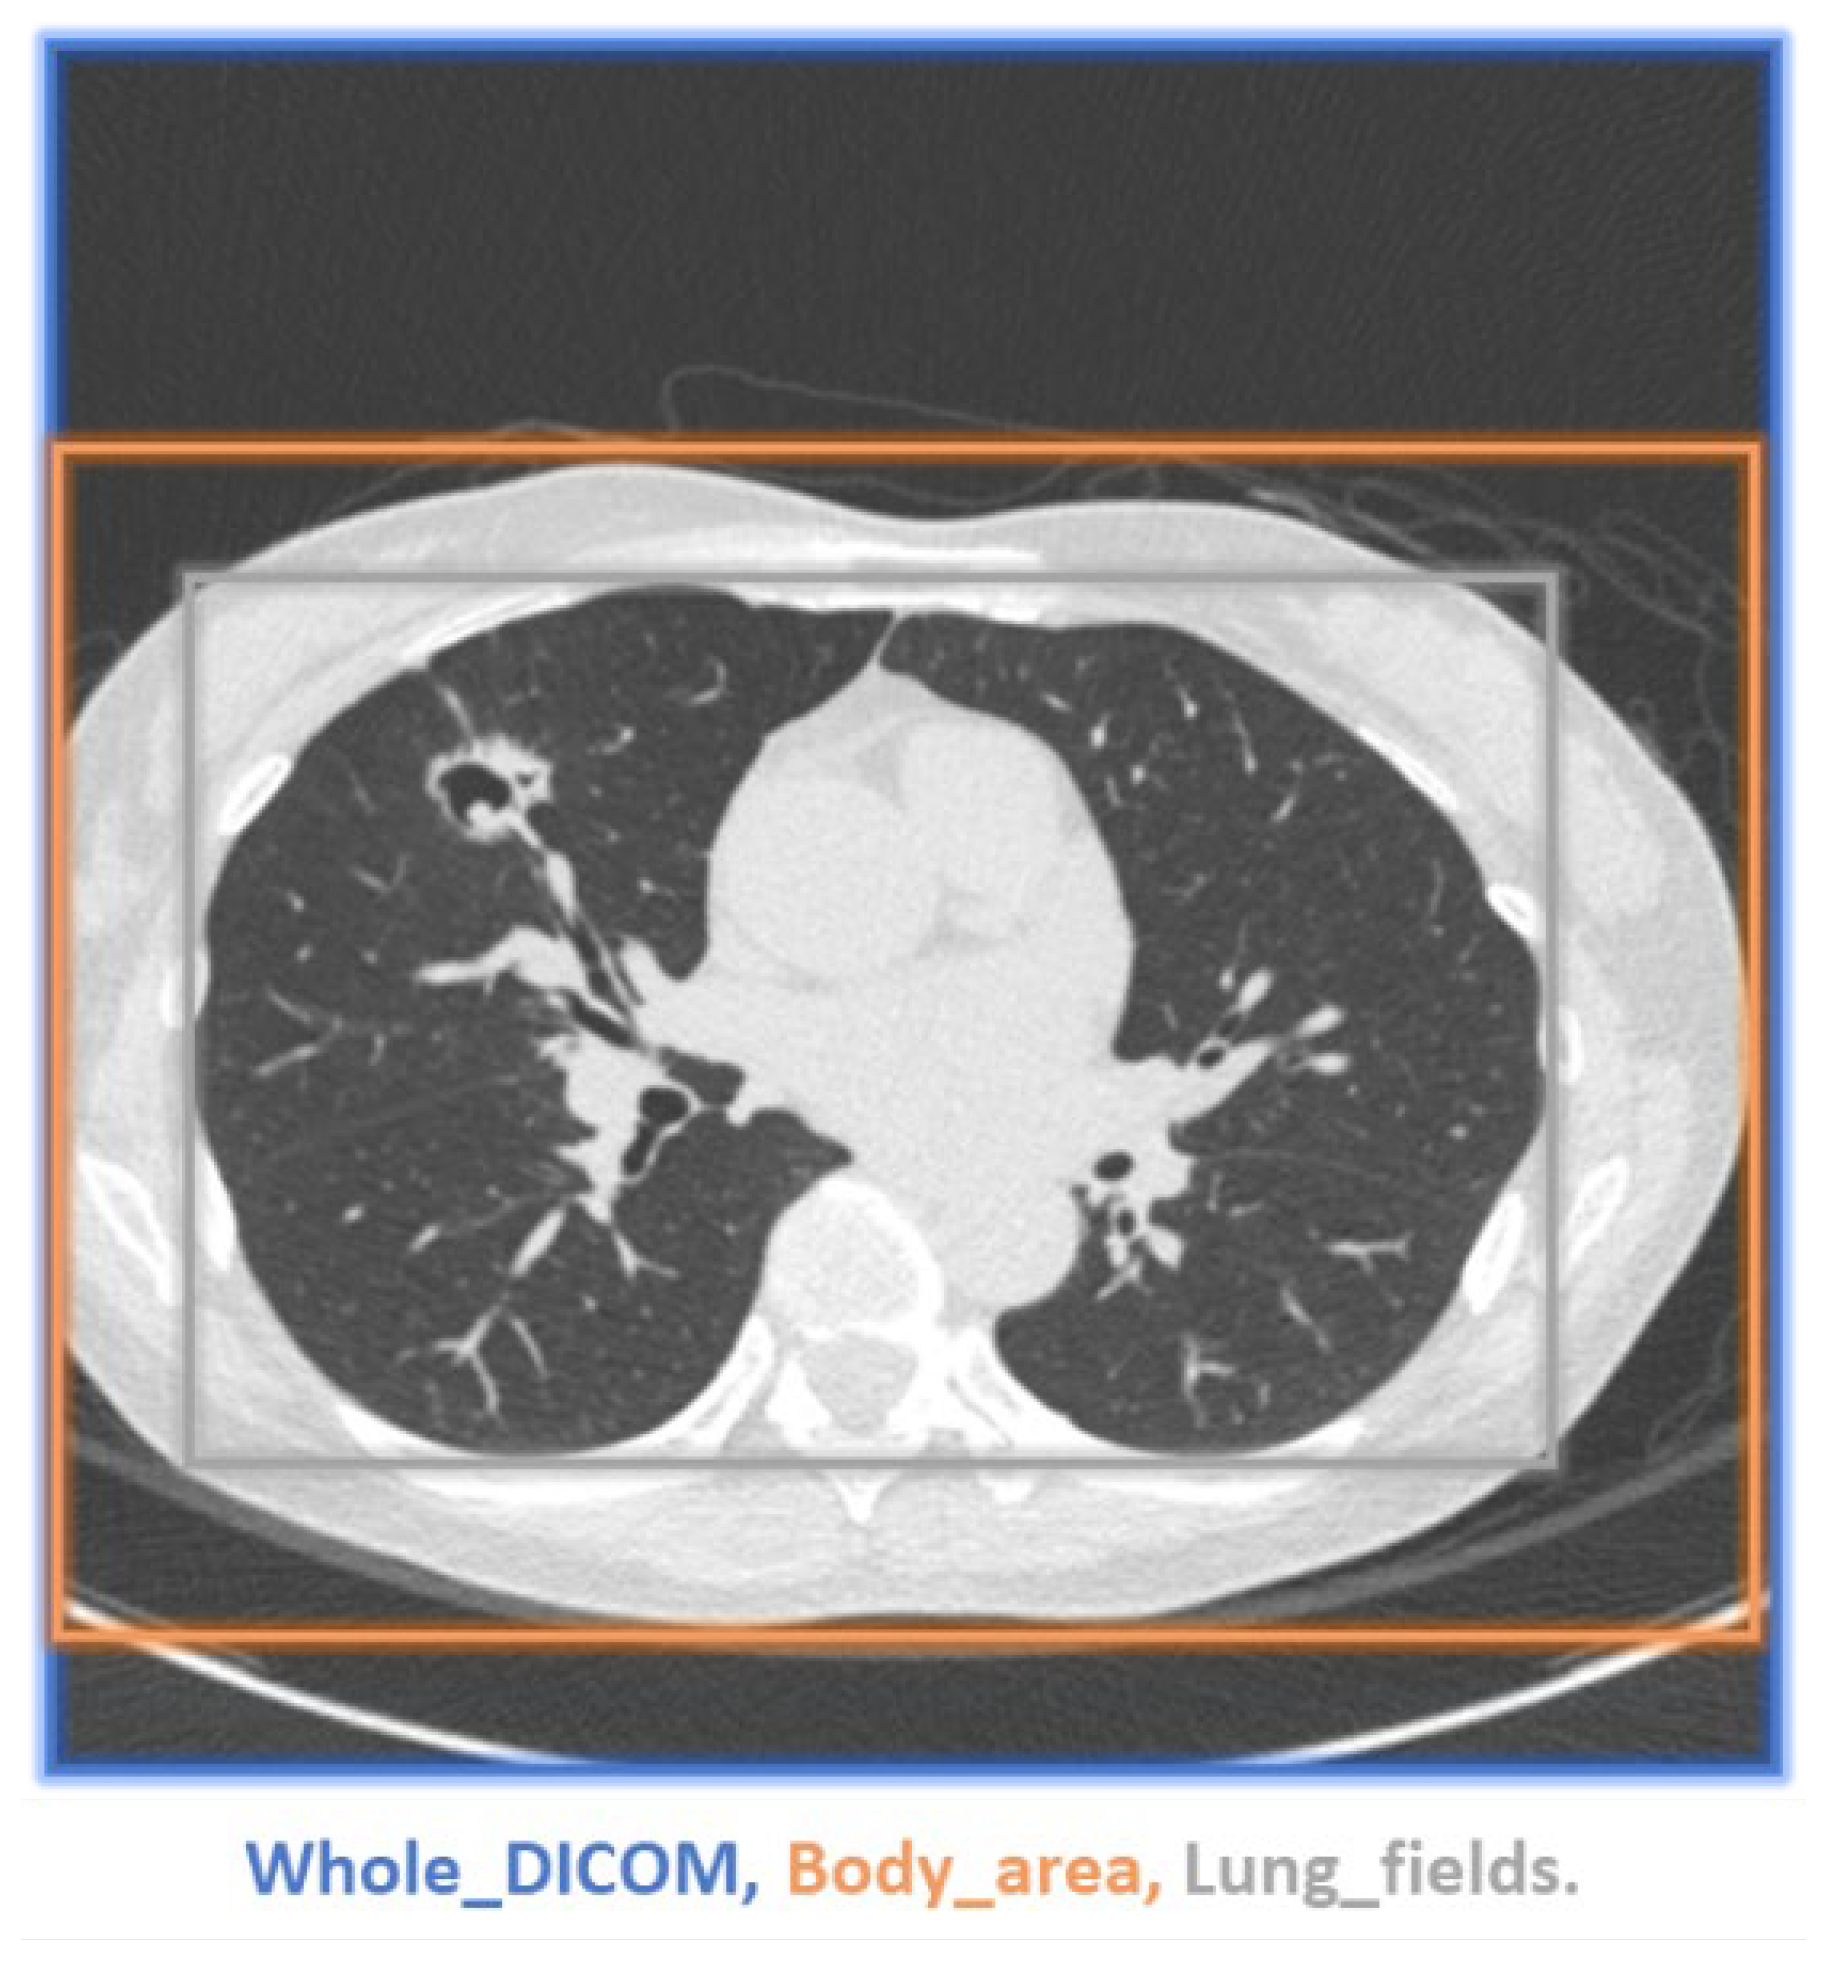

A demonstration of the proposed method for selecting an ROI is presented in Figure 11. While the ROI covered the entire images (blue box), we also selected bounding boxes for the body area (orange box) and lung fields (grey box). Smaller bounding boxes ignored most of the ambient air and focused on the structures we were interested in. As expected, more uniform black ambient air areas increase the PSNR and SSIM. When the entire image was included in the calculation, the PSNR and SSIM values were relatively high, whereas the lung field bounding boxes yielded the lowest values (see Table 7 and Figure 12). Regardless, applying EDSR to the sagittal plane yielded the best results for all three ROIs (see Table 8). Overall, the PSNR and SSIM increased in the same manner, regardless of ROI selection (see Figure 13). One can see that EDSR was superior to the other models on average, but sometimes, SRResNet performs better than EDSR.

Figure 11. Demonstration of ROI selection. Blue box: whole DICOM image; Orange box: body area; Gray box: lung fields.